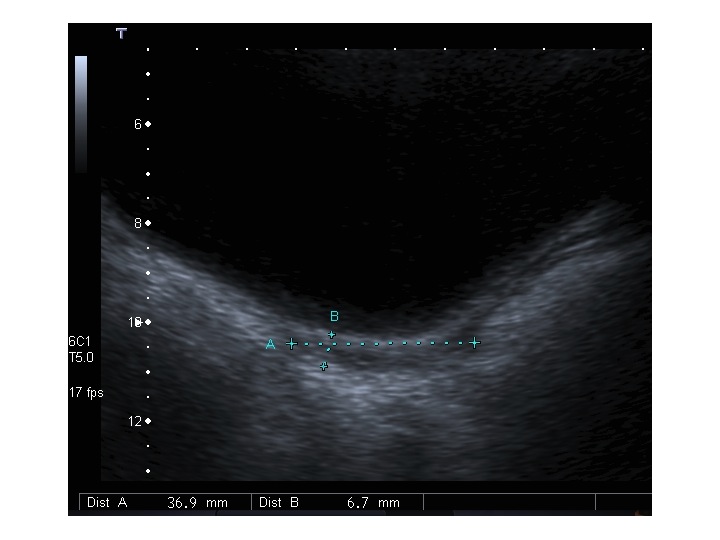

All’ecografia pelvica si osservano le ovaie a “banderella” (figura) e il cariotipo rivela l’assenza di un cromosoma X o la presenza di un mosaicismo, 45 X0/46XX nella forma più comune; nel 5% dei casi di ST può essere presente un frammento di cromosoma Y.

Dopo l'induzione di pubertà è ben visibile la rima endometriale (nella paziente 2 era appena accennata anche nelle immagini pre-terapia), soprattutto nelle sezioni longitudinali, con l'assenza di follicoli a livello ovarico